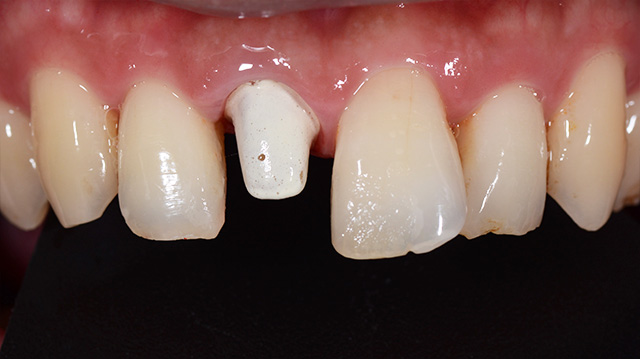

| 年代・性別 | 50代 男性 |

|---|---|

| 主訴 | 転倒して歯が割れた |

| 治療回数 | 3回 |

| 治療期間 | 約1ヶ月 |

| 費用 | 仮歯 5,500円 ジルコニアクラウン 176,000円 |

*キャンセルポリシーをご一読のうえご予約ください